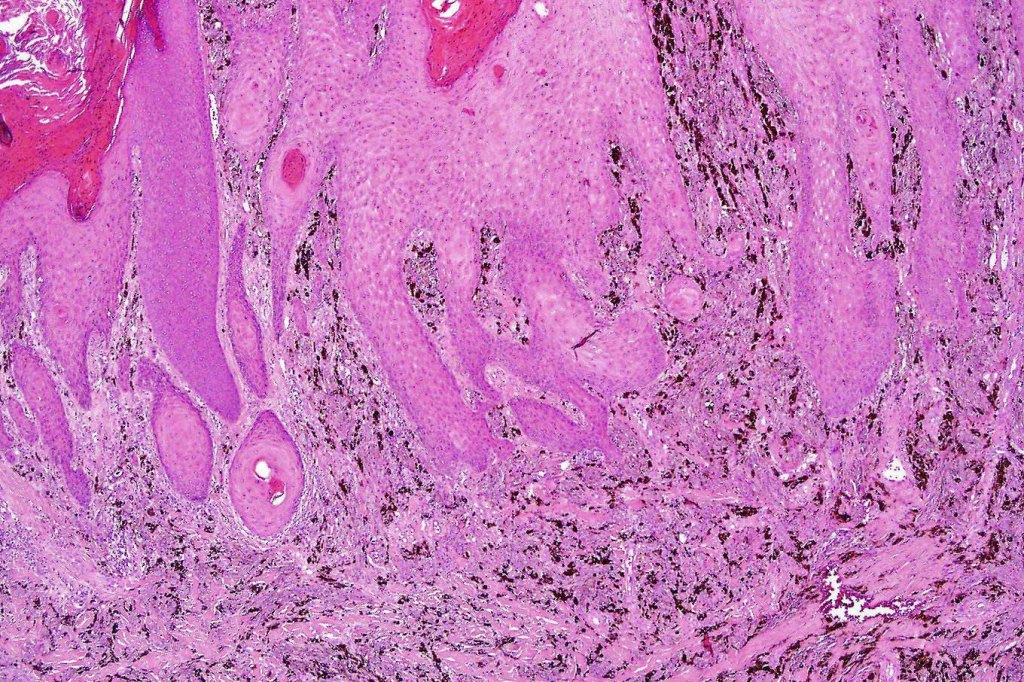

•Dermal of less often compound

•Wedge shape or less often plaque like silhouette

•Commonly associated with marked acanthosis/pseudoepitheliomatous hyperplasia although much less commonly, the epidermis is strteched over the lesion

•Composed of an admixture of large epithelioid melanocytes with vesicular nuclei containing a very prominent nucleolus (fried egg cells), spindle cells, dendritic cells & melanophages